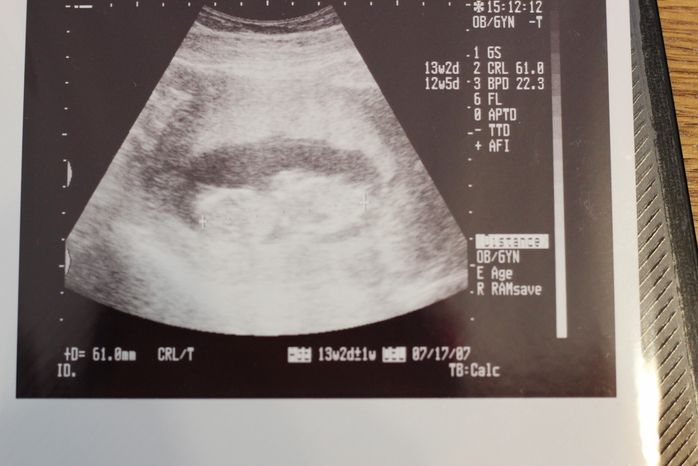

妊娠13週目のエコー写真

こちらを向いて横たわっているように見えます。自分のおなかがタヌキのおなかみたいだったので、赤ちゃんに「ぽん太」と名付けて話しかけたり、一緒に歌ったり、踊ったりしていました。